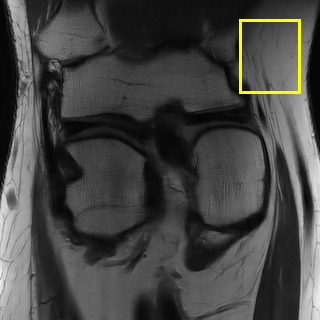

Edge preserving has always been a crucial concern in the design of reconstruction models. To improve the quality of reconstructed images and preserve image edges, some works suggested introducing edge priors in the original restoration problem to preserve image edges [4, 34]. However, they will suffer from complicated algorithm design and time-consuming training processes. Recently, some more efficient methods have been proposed to use edge maps as external guidance for image restoration. For example, Yang et al. [48] used off-the-shelf edge detectors to extract image edges from the degraded images. Fang et al. [12] predicted image edges by constructing an edge reconstruction network. Huang et al. [18] designed a novel dual discriminator GAN framework for solving fast multi-channel MRI, in which one GAN network is built for edge information enhancement. Inspired by these methods, we also consider introducing image edge prior as external guidance to MRI reconstruction since 1) image edges are prominent and distinguishable features in MRI (see Fig. 1), which can serve as a good guide to the model to recover high-frequency details; 2) the ground truth edges can be easily fetched via ordinary edge extraction operators, like Canny, Sobel, and Prewitt, which means that the edge maps can be learned in a data-driven manner. However, how to effectively utilize image edge priors to guide image reconstruction still remains a challenge. In some methods, edge information was simply concatenated with the input image and passed to the next stages. Though this is a simple way to utilize the edge priors, it may not give full play to the guiding role of the edge priors. Therefore, in this work, we want to explore a more efficient and effective mechanism to fully take advantage of image edge priors.

fastMRI is a large-scale MR dataset jointly established by Facebook AI Research and NYU Langone Health. It provides both knee and brain datasets for evaluation. In our work, we use the multi-coil knee dataset, which was acquired on three clinical 3T systems or one clinical 1.5T system using a 15-channel knee coil array. The dataset includes data from two pulse sequences, yielding coronal proton-density weighting with (PDFS) and without (PD) fat suppression. As is shown in Fig. 1, PD images usually contain more structural and prominent edge features than PDFS images, which suggests that it is more challenging to use edge guidance on PDFS datasets. Therefore, we explore the effectiveness of EAMRI on these two modalities. Following [13], for both PD and PDFS knee datasets, we separately filter out 227 volumes (8332 slices) for training and 24 volumes (1665 slices) for testing. The dataset is centrally cropped to .

In Table 2, we provide the quantitative results of all the models over three multi-coil datasets: Calgary [37], fastMRI PD [50], and fastMRI PDFS [50]. According to the table, we clearly observe that EAMRI achieves the best performance over all these datasets under both AF 4 and AF 6. For the T1-weighted images (Calgary) and the PD images (fastMRI PD), whose edge features are more prominent and structural (see Fig. 1), EAMRI can achieve high-performance gain when compared with the second-best model. For example, when the AF = 4, PSNR is boosted by 0.64 over Calgary, and 1.26 over fastMRI PD. On the other hand, for the PDFS images under AF 4, PSNR is boosted by 0.22 when comparing EAMRI with the second-best model. This is because PDFS images usually contain more broken edges, which is more challenging to use the edge guidance mechanism. Fortunately, our EAMRI can still achieve better results, thanks to its well-designed network structure and edge priors.